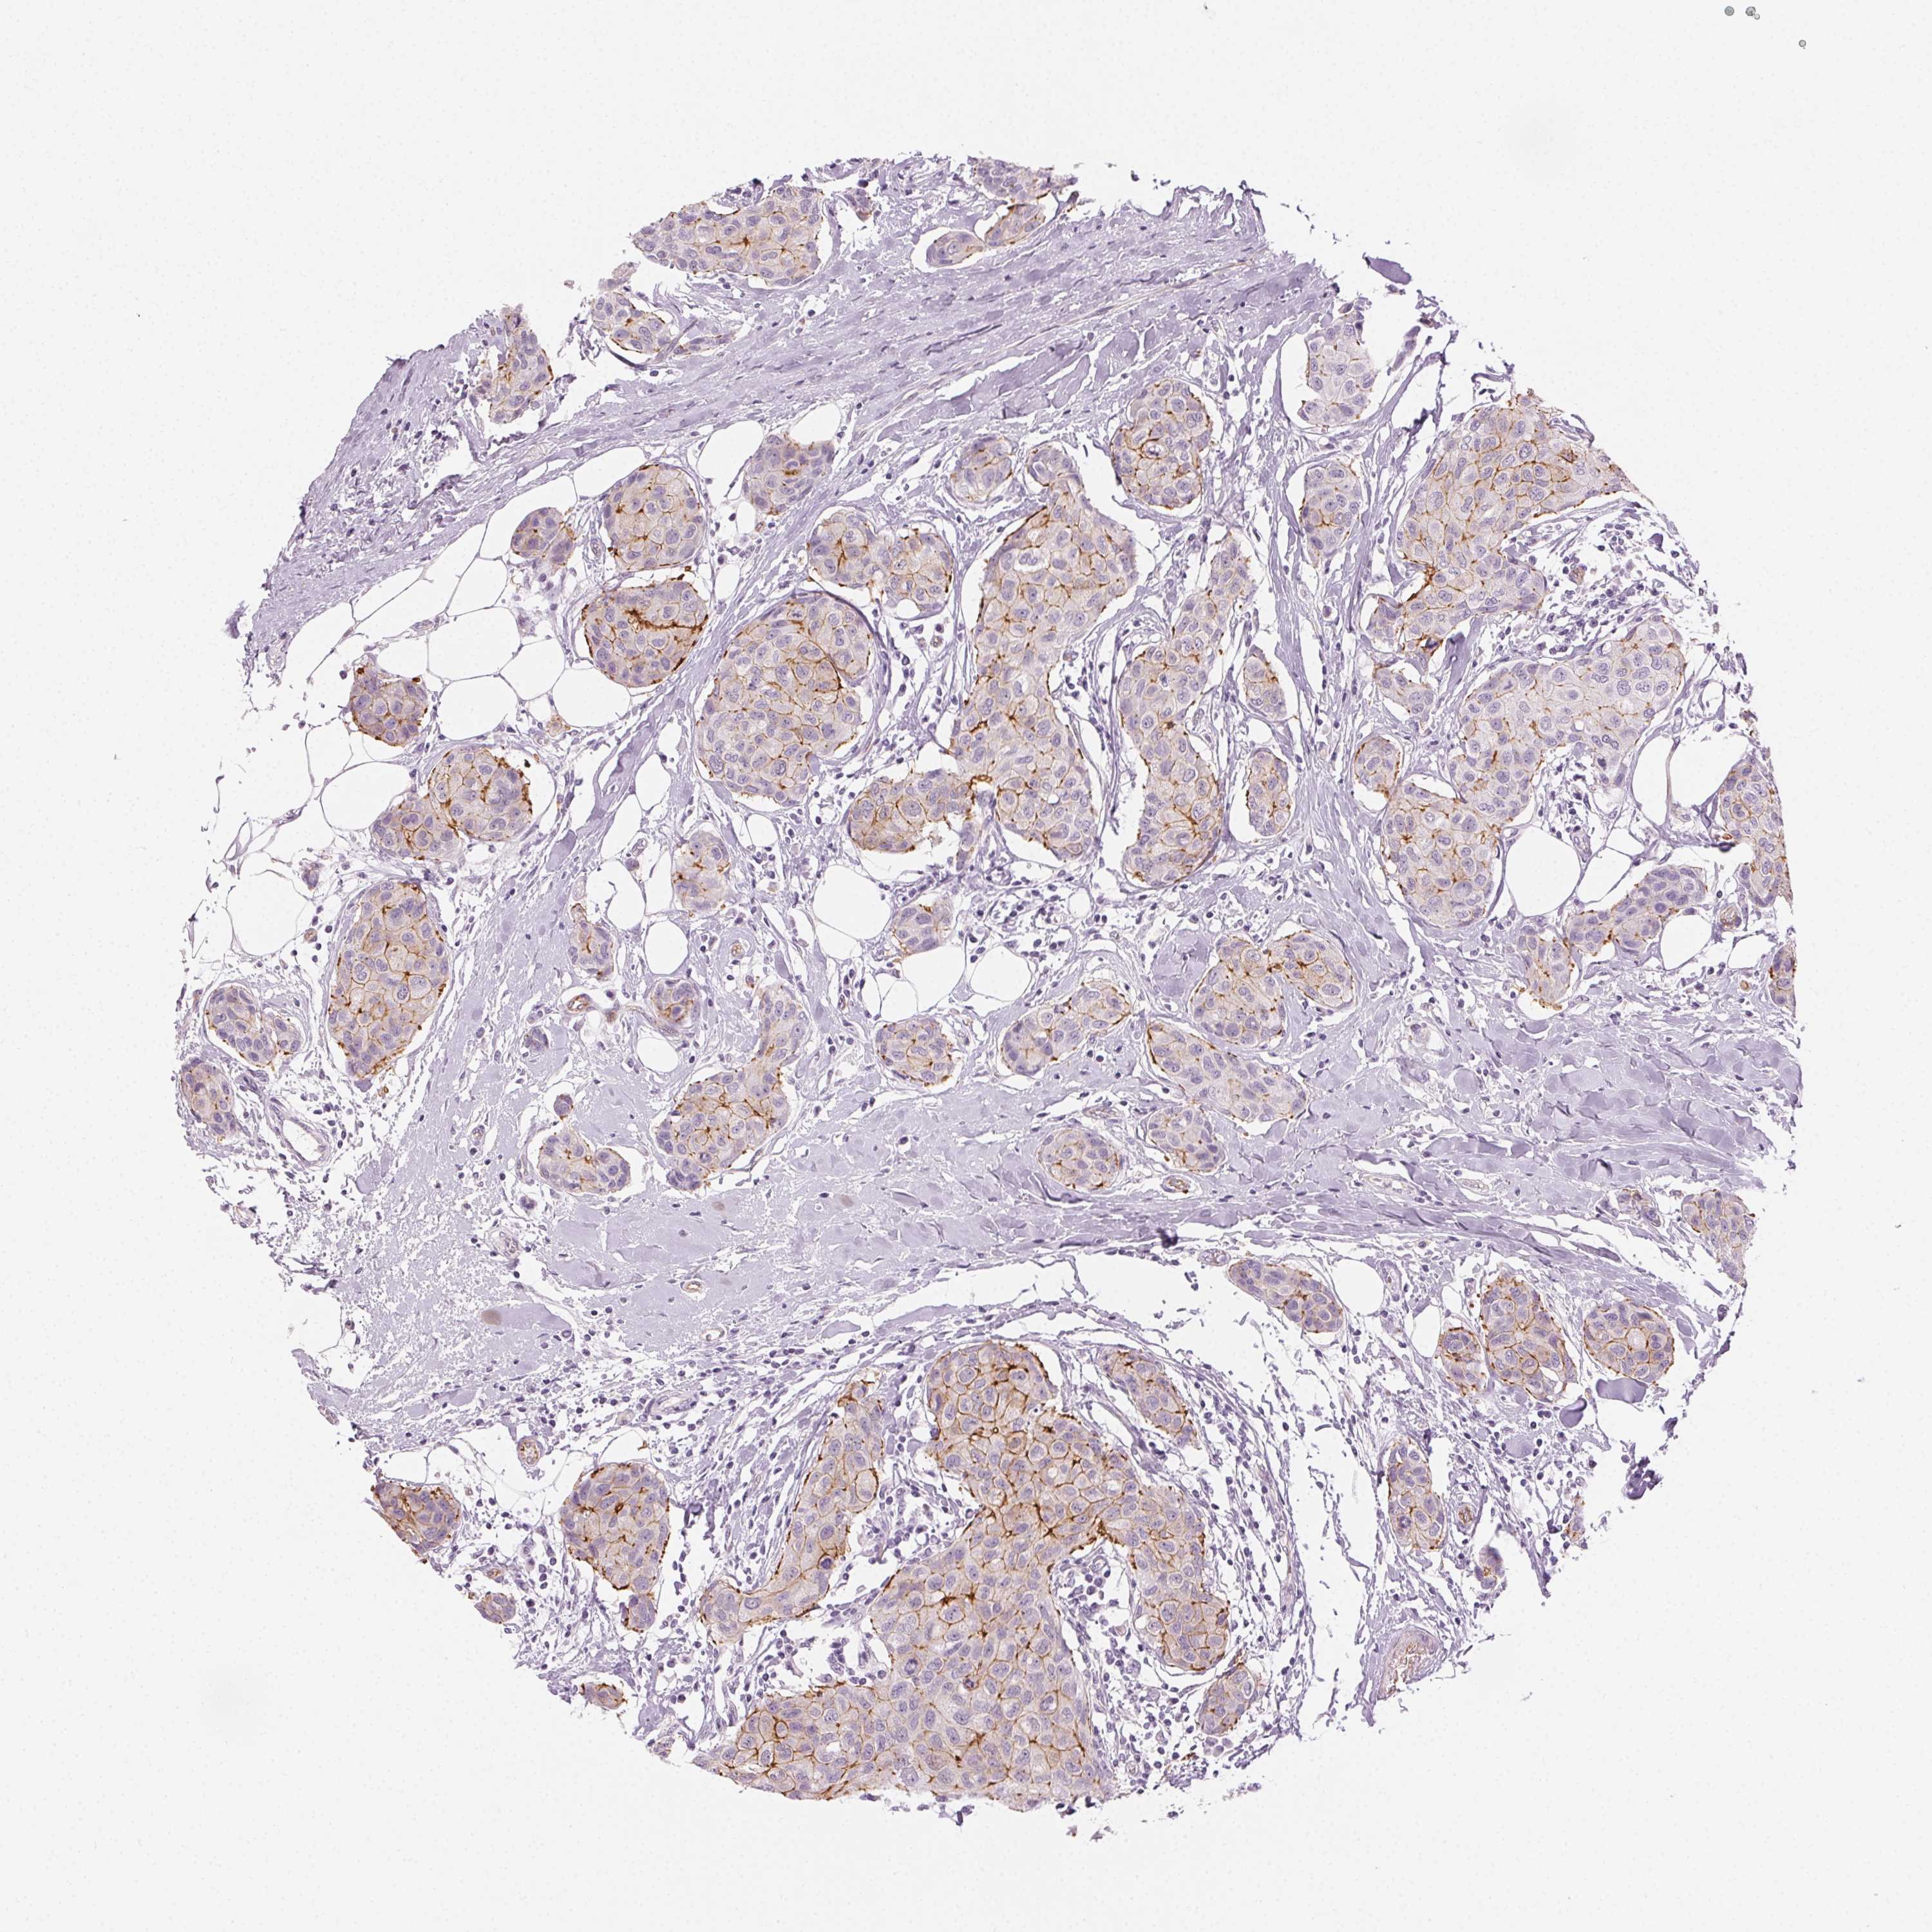

BRCA TCGA BRCA VALIDATION PROTEIN EXPRESSION